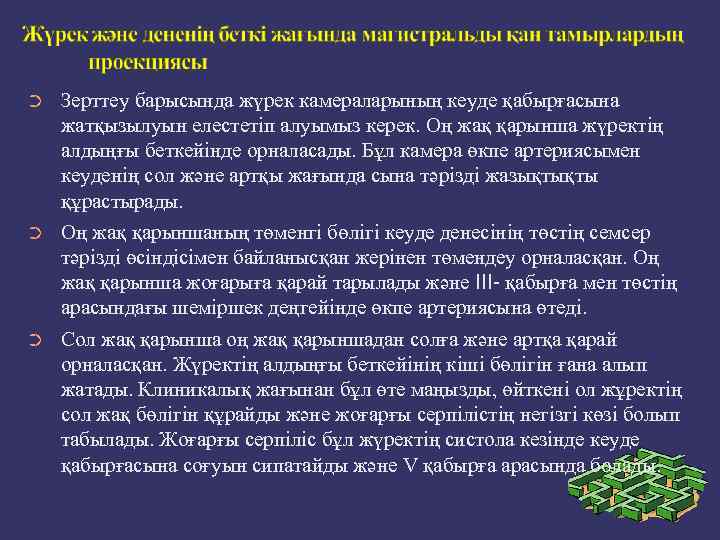

➲ ➲ ➲ Зерттеу барысында жүрек камераларының кеуде қабырғасына жатқызылуын елестетіп алуымыз керек. Оң жақ қарынша жүректің алдыңғы беткейінде орналасады. Бұл камера өкпе артериясымен кеуденің сол және артқы жағында сына тәрізді жазықтықты құрастырады. Оң жақ қарыншаның төменгі бөлігі кеуде денесінің төстің семсер тәрізді өсіндісімен байланысқан жерінен төмендеу орналасқан. Оң жақ қарынша жоғарыға қарай тарылады және III- қабырға мен төстің арасындағы шеміршек деңгейінде өкпе артериясына өтеді. Сол жақ қарынша оң жақ қарыншадан солға және артқа қарай орналасқан. Жүректің алдыңғы беткейінің кіші бөлігін ғана алып жатады. Клиникалық жағынан бұл өте маңызды, өйткені ол жұректің сол жақ бөлігін құрайды және жоғарғы серпілістің негізгі көзі болып табылады. Жоғарғы серпіліс бұл жүректің систола кезінде кеуде қабырғасына соғуын сипатайды және V қабырға арасында болады.

Митральды қақпақ (сол жақ жүрекше - қарыншалық қақпақ) төстің III қабырғамен түйіскен жерінде проекцияланады. Қолқа қақпағы төстің III қабырғаның сол және оң жақтарындағы шеміршектерінің бекіністерінің ортасынан жүргізілген сызықтың ортасында проекцияланады.

➲ Жоғары серпілістің перкуссиясынан кейін пальпациялық анықтауды өткізу керек – ол жүрек ұшының сол жақ бетіне сәйкес келеді. Жоғары серпіліс қалыпты жағдайда V қабырға аралық деңгейде 1 -2 см ішке қарай сол жақ ортаңғы бұғана сызығында орналасқан. Гипертрофия және сол жақ қарыншаның дилатация кезінде жоғарғы серпіліс қалыптастырғанда, оның локализациясы және негізгі сапасын өзгереді. Бұндай сапаға ені, биіктігі, күші және резистенттілігі жатады. Жүрек серпілісі қалыпты жағдайда пальпацияланбайды. Оң жақ қарынша гипертрофиясында ол төстің сол жағында пальпацияланады. Кеуде жасушасының пальпация кезіндегі тітіркенуі – “мысық миялауы“ жүрек ұстамасына тән болады. Аорта пульсациясы, эпигастриальды пульсация, бүйрек пульсациясы қалыпты жағдайда табылмауы керек.